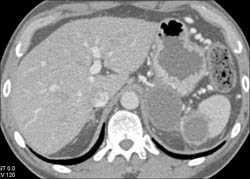

Diagnosis

Islet Cell Tumor